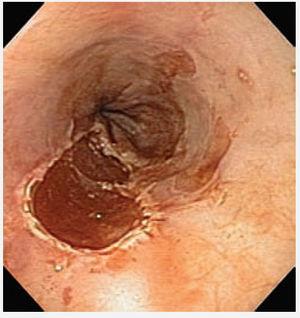

Paciente masculino de 55 años de edad, con enfer-fue sometido a mucosectomía endoscópica con medad por reflujo gastroesofágico. Se realizó pa-técnica de ligadura (figura 2). La endoscopia de nendoscopia, identificándose esófago de Barrett de control mostró tejido esofágico de características segmento largo. La cromoendoscopia digital con normales con signos de cicatrización en el sitio de imagen de banda estrecha (NBI) y magnificación, la mucosectomía (figura 3). El paciente continúa reveló zonas con un patrón tipo Pit IV de la clasi-en protocolo de vigilancia de displasia y con trataficación de Endo1 (figura 1). Las biopsias revelaron miento con inhibidor de bomba de protones. un foco de displasia de alto grado y el paciente

Figura 2. Imagen endoscópica posterior a mucosectomía esofágica en la zona correspondiente a displasia de alto grado en esófago de Barrett.